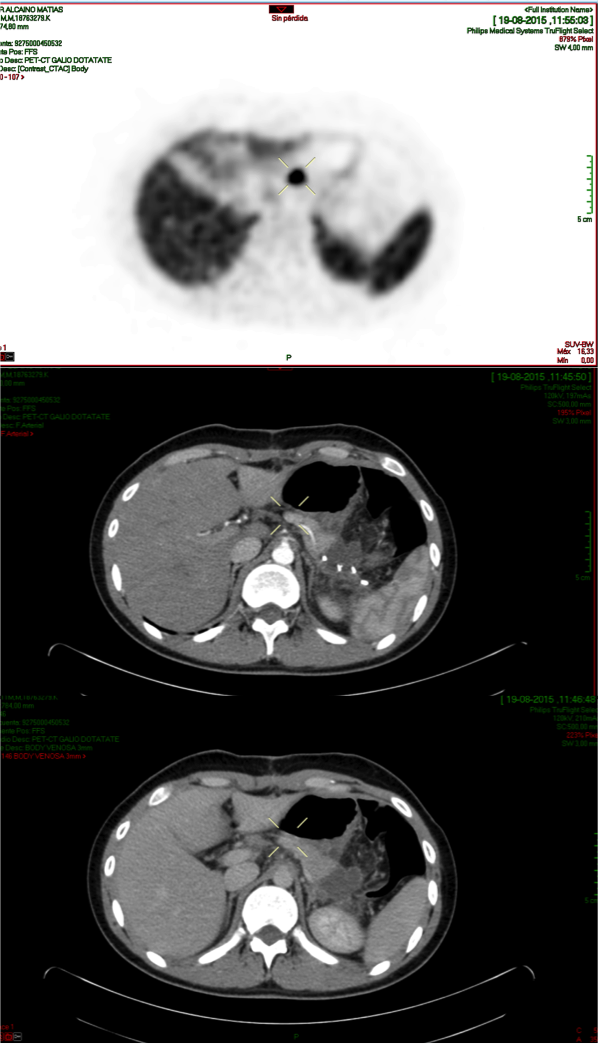

Male, 20 y/o, with hypoglycemia operated on twice of insulinoma. Asymptomatic, MR showed a possible lesion in the pancreas. It was requested PET-CT withGa68 DOTANOC. A nodule is seen in the body of pancreas, 15 mm, SUV max of 29 (cross in transaxial slices). The upper CT slice shows the arterial phase with nodular enhancement and at the bottom the venous phase, (cross both in PET and CT images).